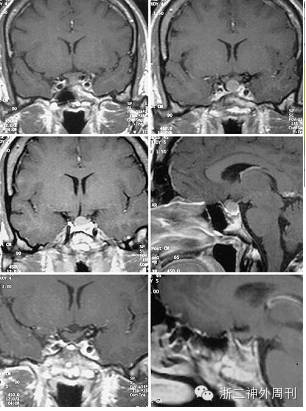

还有一位8岁男孩,因性早熟和发现鞍上区肿物就诊,后证实肿物为GCT[4];更有意思的是,Losa报道一例肢端肥大症的42岁女性,术后病理证实肿瘤为GCT(图6),作者甚至认为GCT可能分泌GH,导致患者出现相关内分泌症状[5];Mumert等还报道过一例似Rathke囊肿的囊性GCT[6](图7)。本例病人为老年男性患者,平素体健,在偶然的一次体检中发现此鞍上病变,根据病史及影像学表现,我们一开始亦考虑诊断为脑膜瘤和颅咽管瘤,后经术中所见和术后病理分析,确诊为GCT。因此,对于术前临床症状不明显、病变位于鞍上/垂体柄部位、术中肿瘤质地较坚韧的鞍区病变患者,需怀疑GCT可能。

图6. 上方及中间共4图,显示一例术前表现为肢端肥大症的42岁女性GCT患者MRI,肿瘤位于垂体上方;下方2图为术后5个月MRI检查结果[5]。